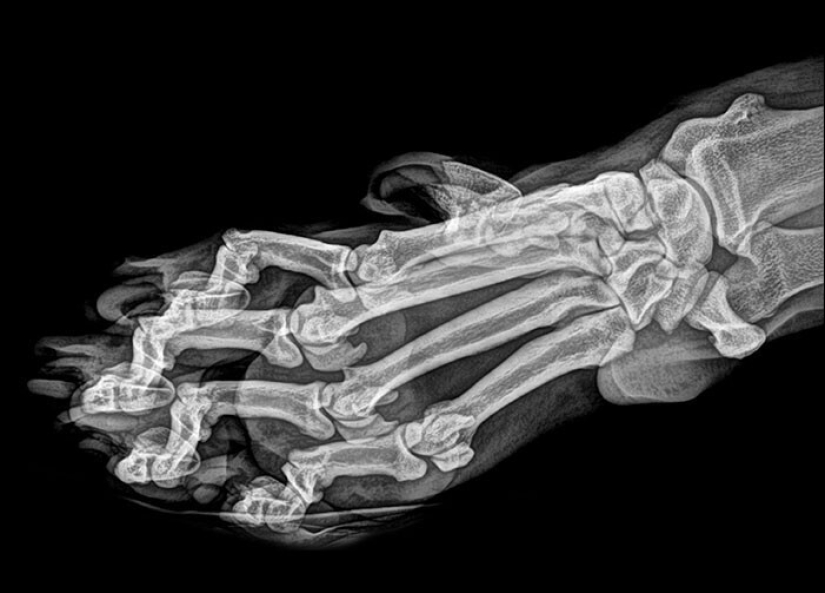

Tiger paw